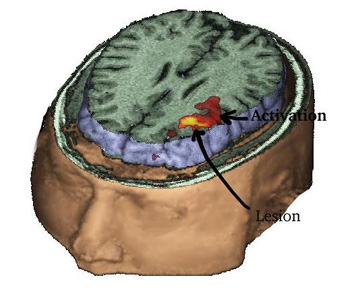

Caso 3

Niño diestro de 13 años de edad con epilepsia del lóbulo temporal. Se detectó un oligodendroglioma multiquístico en el lóbulo temporal izquierdo (flechas negras). Se indicó una IRM para llevar a cabo un mapeo de las áreas del lenguaje antes de la resección quirúrgica.

Una IRMf tridimensional muestra la masa en el polo temporal izquierdo. La activación se obtuvo mediante un paradigma de "tarea de repetición" (burbujas de color amarillo, anaranjado y rojo). La relación entre la lesión y las áreas del habla se muestra magníficamente.